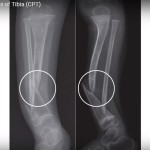

Congenital Pseudarthrosis of Tibia

Courtesy: Mr Michael Uglow FRCSOrth, Paley’s Orthopaedic Institute, UAE